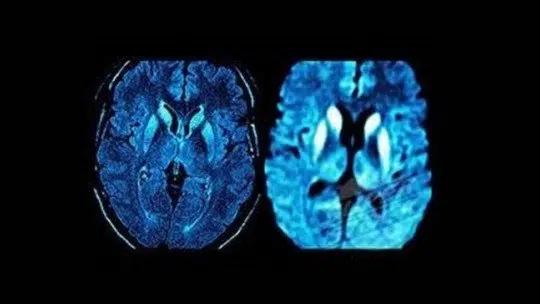

Da mesma forma, uma tomografia computadorizada ou ressonância magnética (MRI) do cérebro pode ser útil para descartar que os sintomas são devidos a outros problemas, como tumores cerebrais, e para identificar padrões comuns na degeneração cerebral da DCJ.

A doença de Creutzfeldt-Jakob (DCJ) corresponde a uma família de doenças denominadas encefalopatias espongiformes transmissíveis (EET). Nestas doenças, os cérebros infectados têm buracos ou buracos perceptíveis apenas ao microscópio ; tornando sua aparência semelhante à das esponjas.